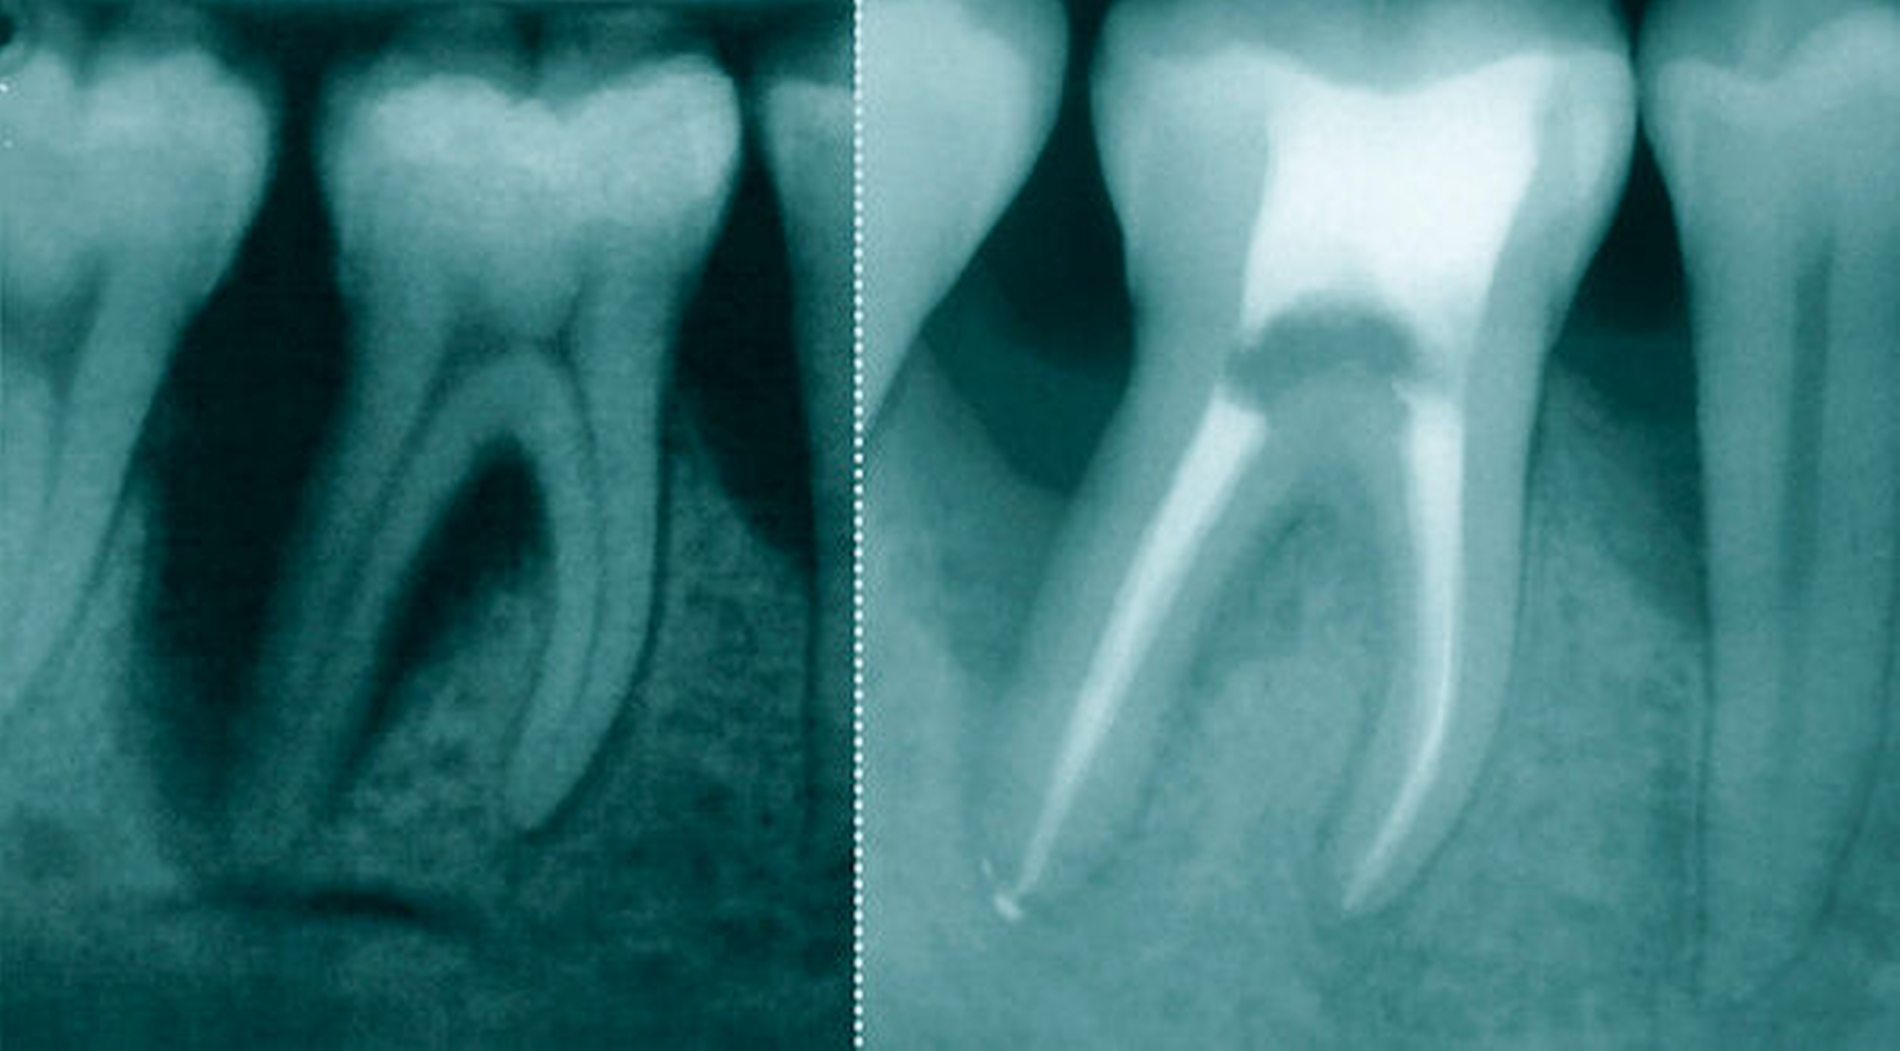

Endo-parodontale Läsionen

Endo-parodontale Läsionen sollten nach Anzeichen und Symptomen klassifiziert werden, die einen direkten Einfluss auf ihre Prognose und Behandlung haben – zum Beispiel die An- oder Abwesenheit von Frakturen und Perforationen und die An- oder Abwesenheit einer Parodontitis.

Falldefinition: Eine endo-parodontale Läsion ist eine pathologische Kommunikation zwischen den Pulpa- und Parodontalgeweben an einem Zahn, die in akuter oder chronischer Form auftreten kann. Die primären Anzeichen, die mit einer solchen Läsion verbunden sind, sind tiefe parodontale Taschen, die bis zur Wurzelspitze reichen und/oder eine negative/veränderte Reaktion auf Vitalitätstests der Pulpa.

(a) röntgenologische Hinweise für Knochenverlust im apikalen oder im Furkationsbereich,

Anzeichen von endo-parodontalen Läsionen im Zusammenhang mit traumatischen und/oder iatrogenen Faktoren können Wurzelperforation, Fraktur/Rissbildung oder externe Wurzelresorption sein. Diese Zustände beeinträchtigen die Prognose des betroffenen Zahnes drastisch.